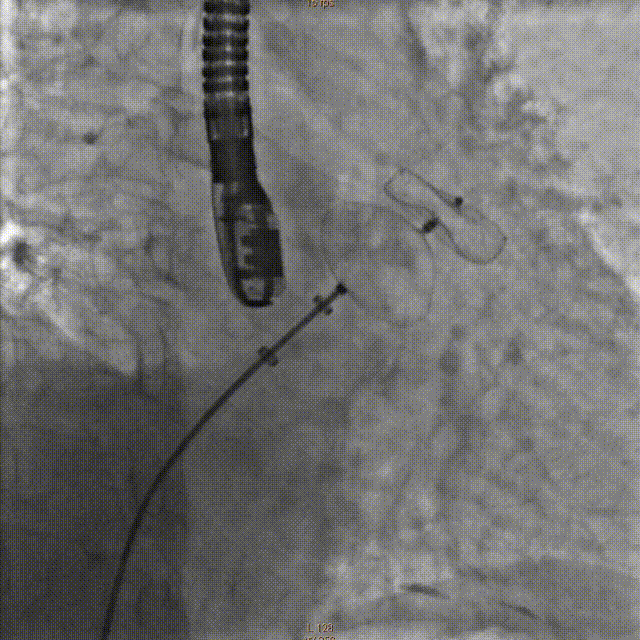

将传输外鞘推送至左心耳开口,结合术前及术中超声检测结果,选择直径26mm左心耳封堵器。严格排气后送入左心耳封堵器,在食道超声及DSARA30°+CAU20°透视下精确定位左心耳封堵器固定盘,造影示位置及封堵良好,透视下释放封堵盘并牵拉,造影及超声检测未见明显漏肩及侧漏,固定盘及封堵盘稳定,贴合左心耳开口好。

释放固定盘并造影